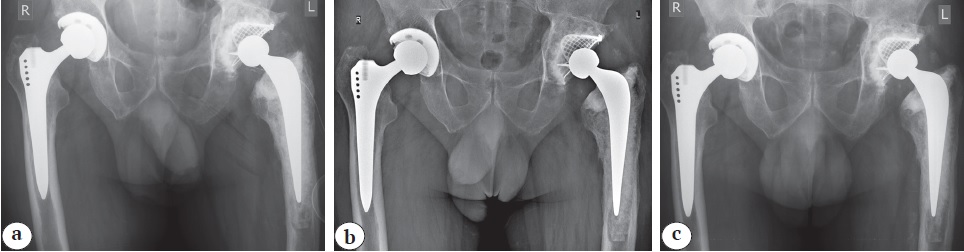

На контрольной рентгенограмме от 03.08.2018 г. после выполненного ревизионного эндопротезирования и реконструкции вертлужной впадины с применением сетки и ИКП, реконструкции проксимального отдела бедренной кости с помощью ИКП и использованием цементной ножки Stryker Exeter костнопластический материал равномерно заполняет вертлужную впадину. Задний край впадины аугментирован реконструктивной сеткой, расположение бедренного компонента правильное, параллельно оси бедренной кости; заполнение бедренного канала костнопластическим материалом равномерное, одинаковой интенсивности во всех зонах. Рентгенопрозрачных линий на границе «костнопластический материал — цемент» не наблюдается (рис. 3 a).

Рис. 3. Обзорные рентгенограммы таза после ревизионного вмешательства на левом тазобедренном суставе: a — контрольная рентгенограмма сразу после операции (02.08.2018): отмечается равномерное распределение костнопластического материала, восстановление центра ротации сустава; b — через 4 мес. (24.12.2018): положение компонентов прежнее, миграции тазового и бедренного компонентов не наблюдается, состояние костнопластического материала удовлетворительное, без признаков резорбции, отсутствие рентгенопрозрачных линий на границе «костнопластический материал — цемент»; с — через 4 года (24.10.2022): рентгенологические признаки перестройки костнопластического материала в тазовой и бедренной костях, отсутствуют линии просветления на границе «костнопластический материал — цемент», положение компонентов эндопротеза прежнее — без признаков миграции или проседания

Fig. 3. Plain pelvis X-rays after the left hip revision: a — control X-ray immediately after the surgery (02/08/2018): even distribution of osteoplastic material, restoration of the center of rotation of the joint; b — 4 months after the surgery (24/12/2018): position of components remains unchanged, no migration of the acetabular and femoral components is observed, the state of osteoplastic material is satisfactory with no signs of resorption; radiolucent lines at the osteoplastic material-cement interface are absent; c — 4 years after the surgery (24/10/2022): X-ray signs of restructuring of osteoplastic material in the pelvic and femoral bones, radiolucent lines at the osteoplastic material-cement interface are absent, position of components remains unchanged with no signs of migration or subsidence

В послеоперационном периоде пациент активизирован, проведен 1-й этап реабилитации. Осложнений не было. Пациент выписан на 14-е сут. после операции с рекомендацией дозированной нагрузки на оперированную конечность в течение 12 нед. Результаты ревизионной операции через 4 мес. и через 4 года представлены на рисунках 3 b и 3 c соответственно.